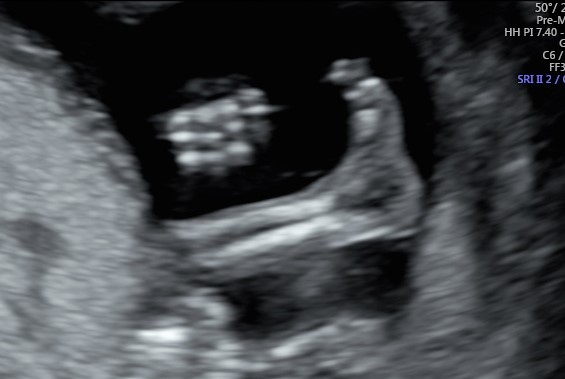

Un piccolo avviso ai naviganti, sapete come calcolare la lunghezza del vostro piccolo? Facile basta moltiplicare la lunghezza del femore per 7 e si otterrà una stima di quanto è alto il tesoro dalla testa ai piedi. Più precise sono le tabelle di riferimento.

In medicina fetale e soprattutto in ecografia è difficile poter fornire certezze, infatti noi procediamo ad approssimazioni e calcolo di probabilità, ma una certezza riusciamo a fornirla, in questa epoca, dando una occhiata attenta in mezzo alle gambe, riusciamo a dire se è modello accessoriato o super accessoriato, ovvero se sarà un “tesoro” o una “tesora”. Mi ricordo che quando ero un utente non sono mai riuscito a resistere alla curiosità, ne ovviamente la mia signora. Ho sempre provato una sorta di ammirazione e anche di invidia nei confronti di quei romantici genitori che riescono a resistere fino alla fine per avere la sorpresa al momento della nascita.